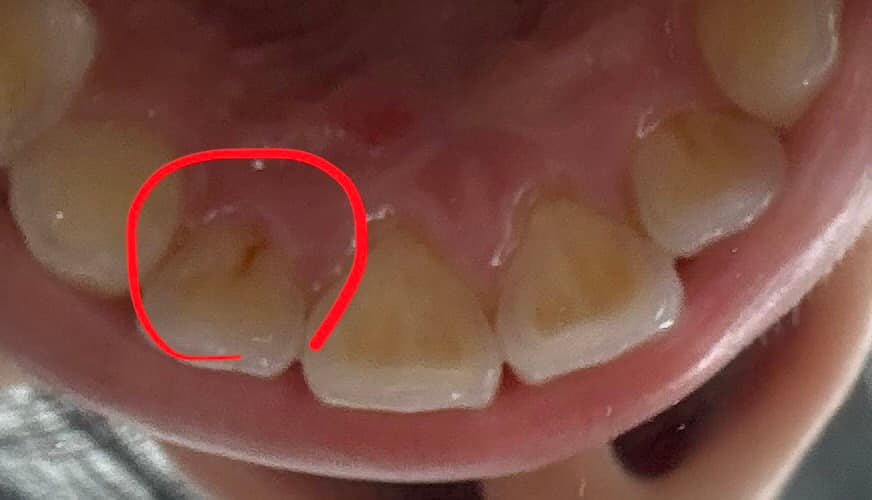

가운데 앞니가 시려서 뒷면을 보던 도중, 시린 앞니가 아니라 그 옆에 앞니에 검정부분이 있는것을 우연히 보게되었습니다. 혹시 충치일까요?

사진에 보이는건 충치인거 같습니다. 치과에 가셔서 검진후 치료를 받아보시는게 좋을것같습니다.

사진으로 봤을 경우에는 충치가 있는 것으로 보입니다. 충치가 있는 경우에는 충치를 제거하고 치과용 재료로 충전해 줘야 할 수 있습니다. 아니 여보세요.

자세한 확인을 위해서 치과에서 진료를 받아보는 것을 권유드립니다.

해당 부분의 사진이 흐릿해 정확한 판단이 어렵지만 충치일 가능성이 매우 큽니다. 앞니 뒤쪽 부위는 치질(치아두께)가 얇아서 충치가 있을 경우에 금방 신경까지 접근할 수 있습니다. 따라서 조기에 발견했다면 미리 치료하는 것이 좋을 수 있습니다.

초기 충치의 양상으로 보입니다. 시린이의 원인이 충치일지는 미지수입니다. 치과가서 엑스레이 찍어보세요